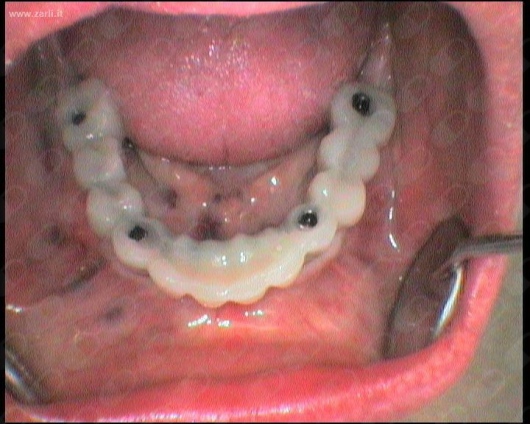

Chirurgia implantologia, Protesi su impianti con chirurgia guidata

• Implantologia